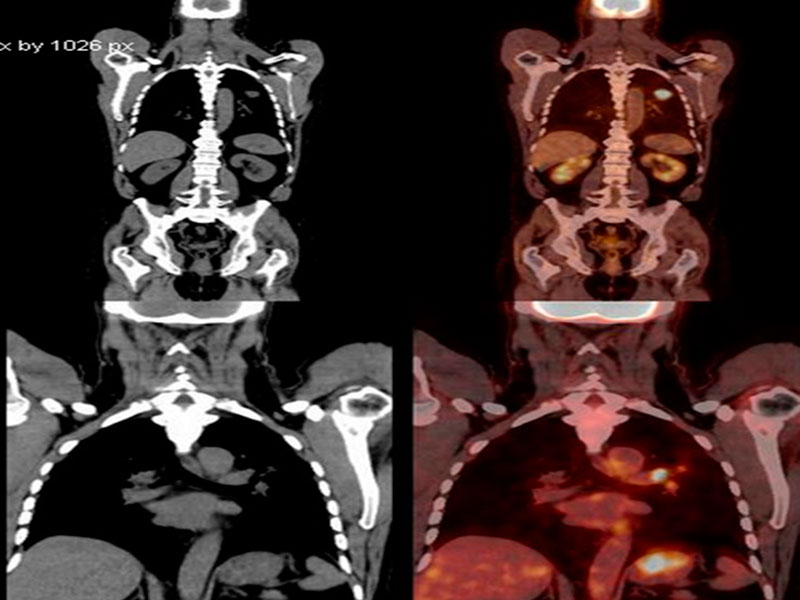

¿Cómo se detecta?

Con una historia clínica anamnesis y examen físico adecuado, así como exámenes auxiliares (rayos X, tomografía)